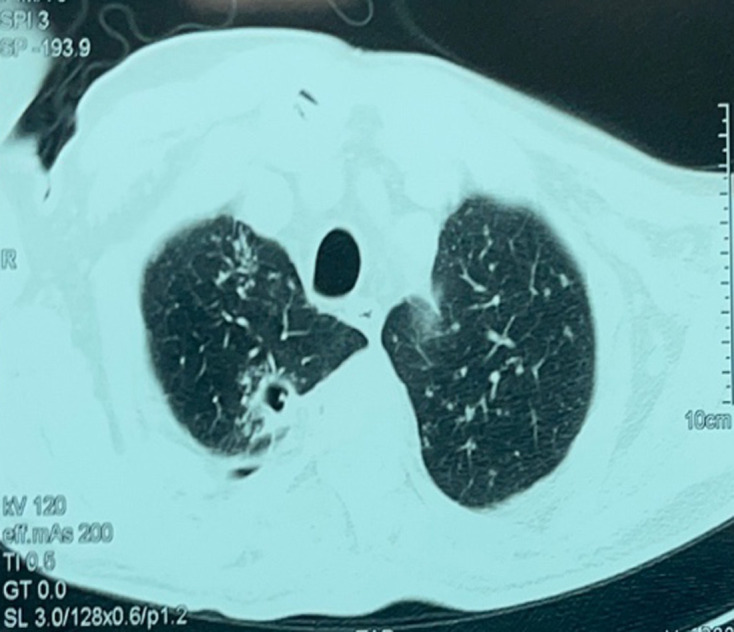

Tuberculosis (TB) is a preventable and usually curable disease but remains a major health problem worldwide, particularly in developing countries. TB of the lumbosacral junction is rare and occurs in only 1-2% of all cases of spinal TB. Moreover, isolated sacrococcygeal TB is extremely rare. We present a case of a 64-year-old patient with a history of diabetes who presented with chronic back pain and cough. Physical examinations revealed a perianal fistula and left elbow joint arthritis. The patient is diagnosed with disseminated TB with coccygeal involvement. Diagnosis was achieved non-invasively using Xpert MTB/RIF, confirming Mycobacterium tuberculosis infection. The patient experienced complete resolution of symptoms following the commencement of anti-TB therapy. We highlight the importance of this case due to the rare coccygeal localization of TB in an immunocompetent patient, diagnosed through non-invasive means.